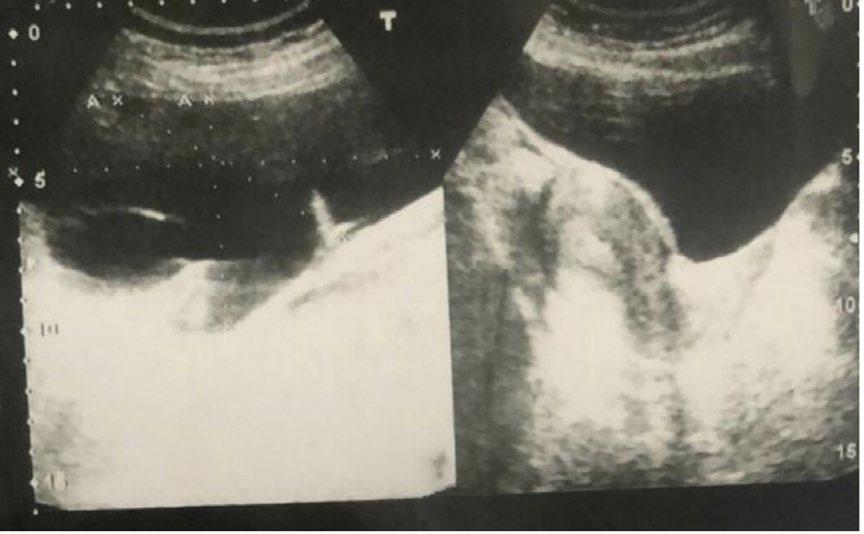

125 All that Torse is Not an Ovary: Ferreting Torsed Subserosal Fibroid in a Flurry of Fibroids: A Case Report

Moharkar et al.